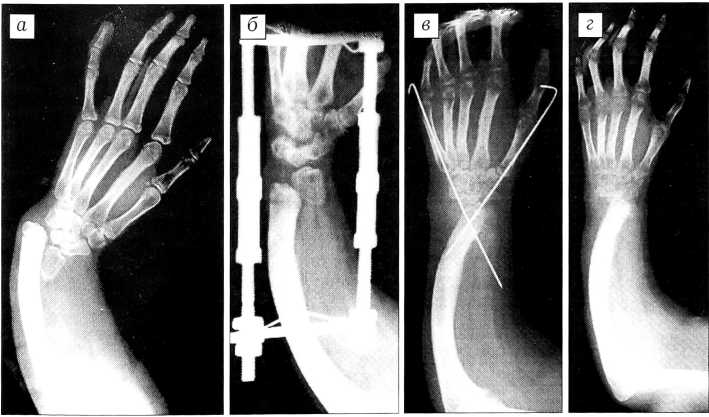

Рис. 2. Рентгенограммы левой верхней конечности больной С. 15 лет с врожденной лучевой косорукостью. а — до операции: в дистальном отделе предплечья гипопластическая лучевая кость; б — в процессе дистракции; в — после операции лучелоктевой суперпозиции с фиксацией кисти спицами Киршнера; г — конечный результат.

Из поперечного разреза по тыльной поверхности предплечья в проекции лучезапястного сустава послойно выделяют дистальный конец локтевой кости и гипопластическую лучевую кость. Производят резекцию проксимальной части лучевой кости и удаляют хрящевой покров с локтевой кости. Вместе с кистью остаток лучевой кости сопоставляют с локтевой. Достигнутое положение транспозиции фиксируют двумя перекрещивающимися спицами Киршнера, проведенными через I и V пястные кости, запястье и сформированную лучелоктевую кость. Рану послойно ушивают и накладывают ладонную гипсовую лонгету (рис. 1).

03.08.99 дистракционный аппарат снят. Из поперечного разреза с тыльной стороны лучезапястного сустава выделена дистальная головка локтевой кости, с которой удален хрящевой покров. Затем выделена рудиментарная лучевая кость и произведена резекция ее проксимальной части на 2/3. Кисть вместе с остатком лучевой кости перемещена на локтевую кость. Достигнутое положение суперпозиции костей предплечья зафиксировано двумя спицами Киршнера. Рана послойно ушита, наложены спиртовая повязка, ладонная гипсовая лонгета.

Спустя 35 дней после второго этапа операции спицы удалены. Гипсовая лонгета заменена на пластмассовый тутор. Проведен курс восстановительного лечения. Функциональный и косметический результат хороший (рис. 2,3).